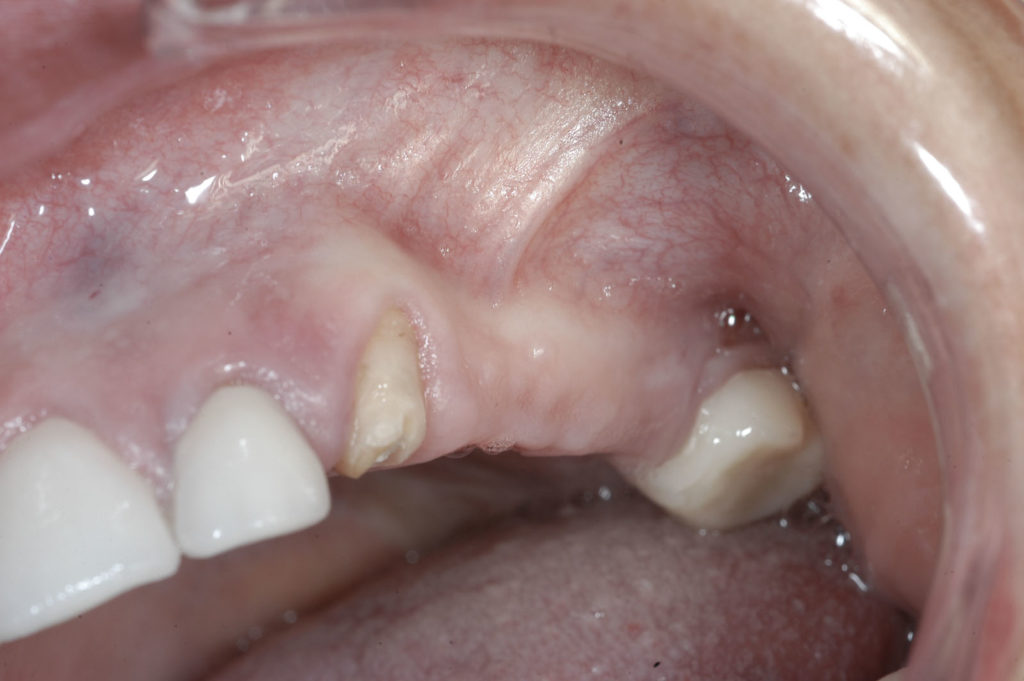

Naturalnym zjawiskiem po utracie zęba jest zanik kości w miejscu po jego usunięciu. W zależności od rozległości zaniku kostnego sytuacja może wymagać dodatkowych procedur, aby zapewnić bezpieczeństwo i długotrwałe powodzenie leczenia implantologicznego.

Zanik kości jest procesem fizjologicznym, który występuje po usunięciu zębów. W ciągu pierwszych 6 tygodni po ekstrakcji zanika do 60% tkanki kostnej. W późniejszym okresie zanikanie spowalnia. Dlatego też im mniej czasu upłynęło od utraty zęba, tym większe szanse na utrzymanie odpowiedniej objętości kostnej dla implantacji, o ile w protokole uwzględnimy zabiegi regeneracyjne. Nie zrekonstruowany w odpowiednim czasie ubytek kostny może powodować zaniki i deformacje, które mocno ograniczają możliwości leczenia implantologicznego.